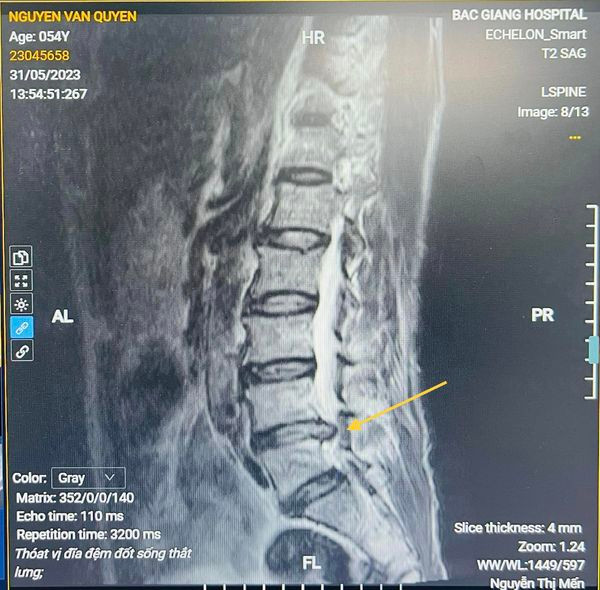

Qua thăm khám và chẩn đoán hình ảnh, bác sĩ xác định ông Q bị thoát vị đĩa đệm cột sống thắt lưng L4-L5, hẹp ống sống, hội chứng đuôi ngựa. Sau khi được bác sĩ tư vấn giải thích về phương pháp điều trị ông đã tin tưởng ở lại bệnh viện để phẫu thuật.

| Hình ảnh thoát vị trên phim chụp - ảnh BVCC |